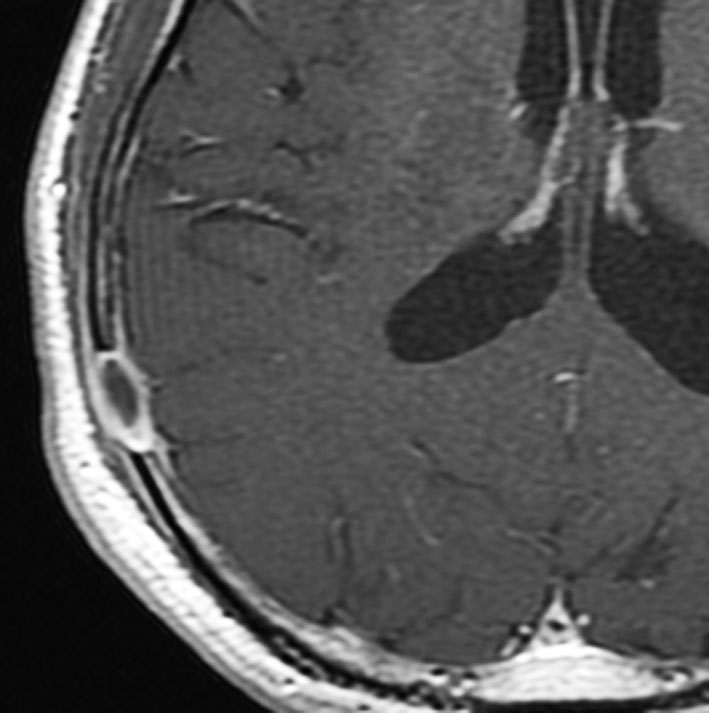

左はMRI T2強調画像です。まるで丸い腫瘍のように見えます。

下のT1強調画像では,ガドリニウム造影剤で強く増強されていて皮下に炎症性腫脹がみられ,活動期の病変であるのがわかります。

この病変は単発(孤発)病変ですが,ややいびつな形をしていて,頭皮の方に盛り上がっていますから,活動性の病変です。手術で完全摘出すると治りますから,骨欠損が広がるようなら手術したほうがいいです。理由は,手術が簡単なこと,病理診断がつくこと,これ以上の病変の広がりを抑えることです。最近は自然の骨に近いような人工骨で補填することができますが,骨形成しなくても自然修復で骨形成されます。とくに,低年齢児では骨形成をしない時もあります,頭蓋骨が自然再生するからです。